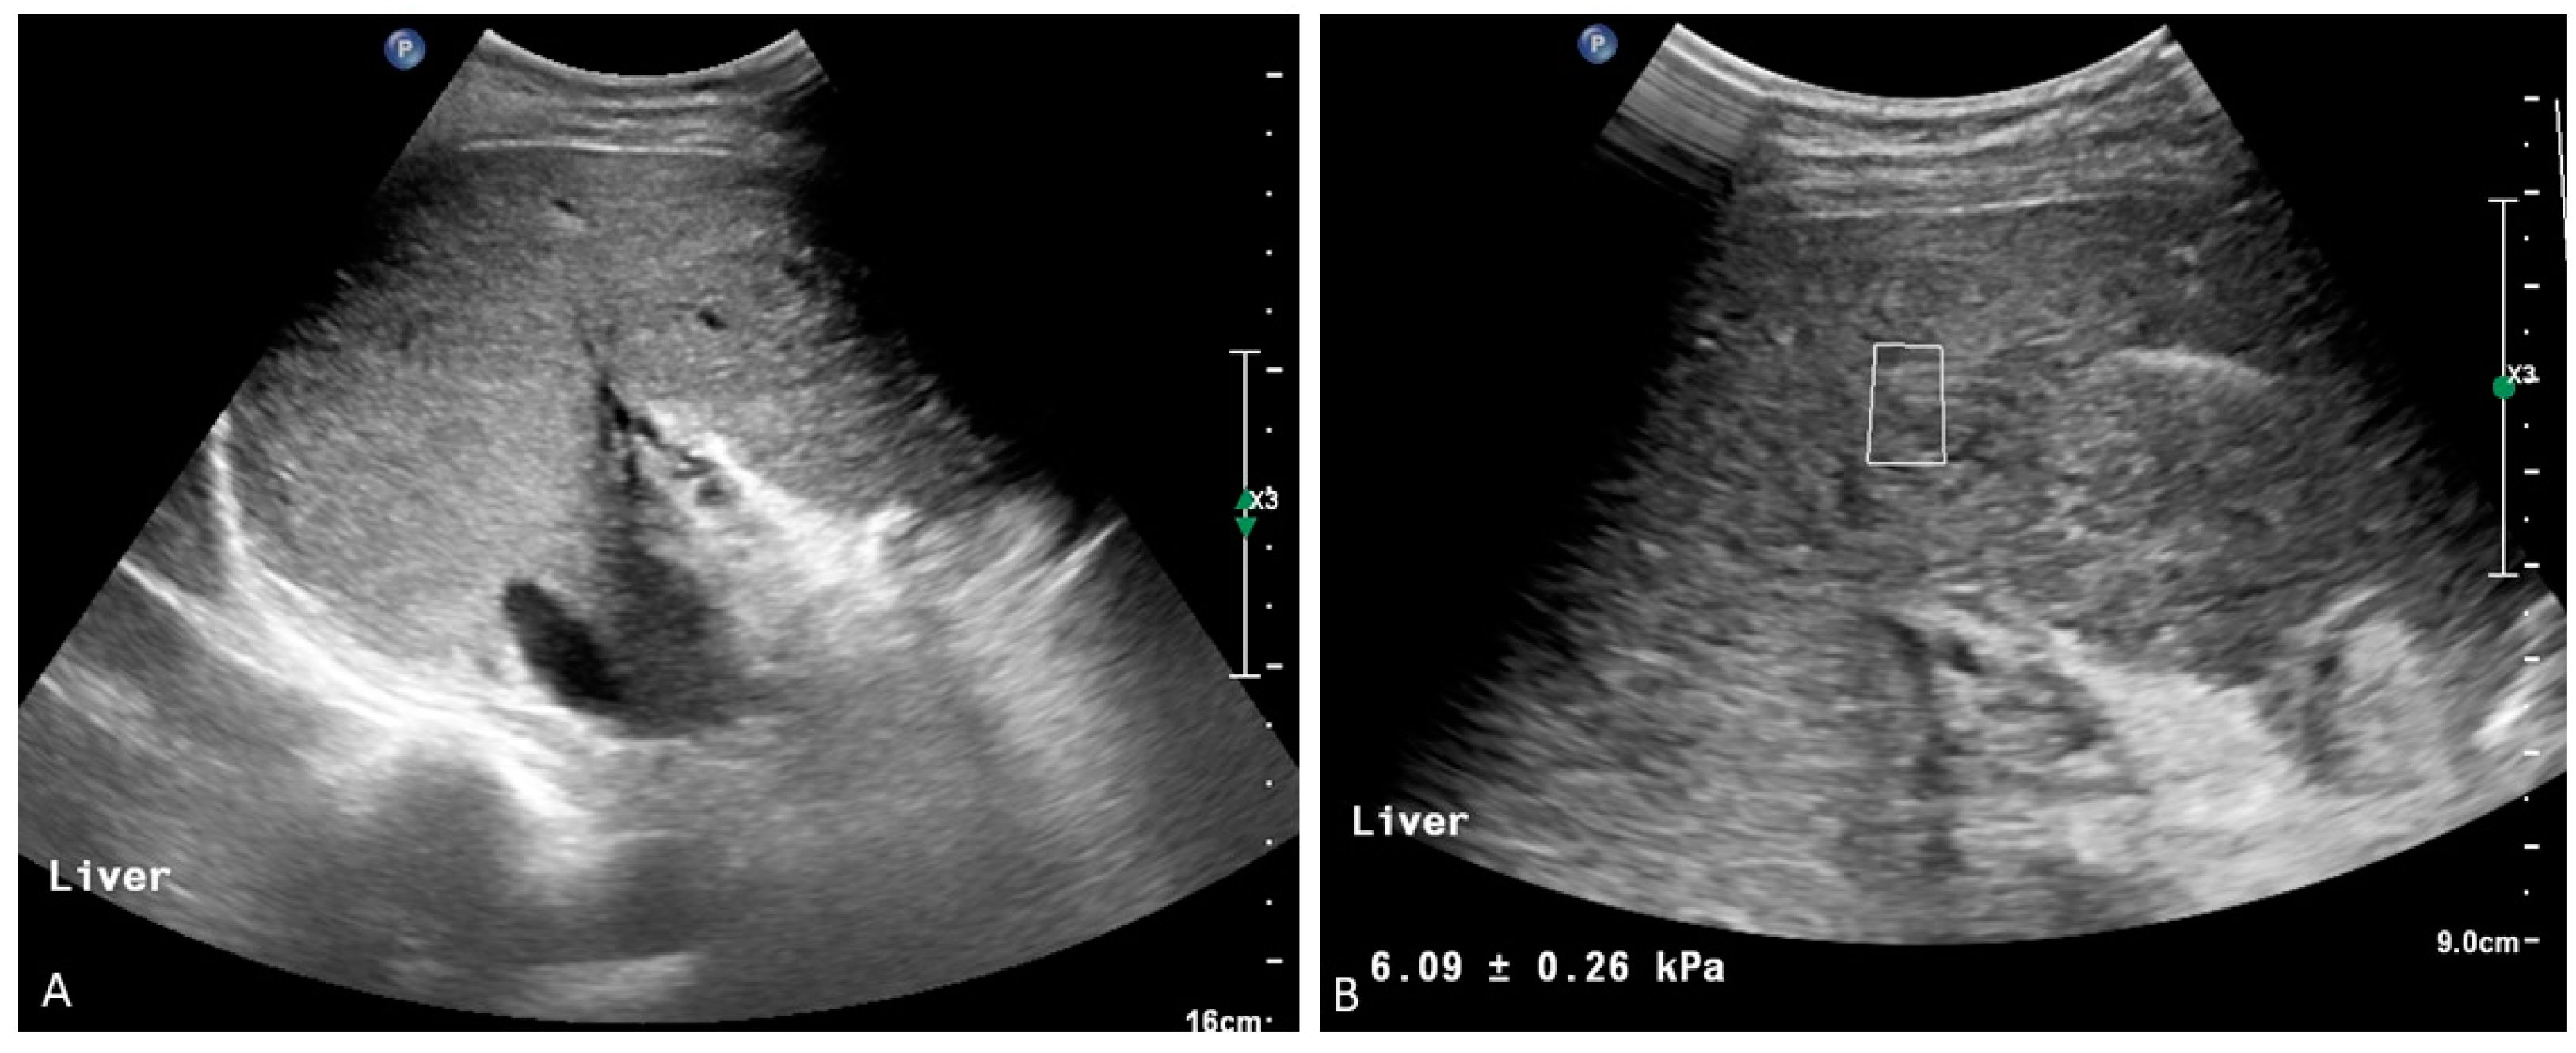

3. Porto-Sinusoidal Vascular Disorder

- De Gottardi, A.; Sempoux, C.; Berzigotti, A. Porto-sinusoidal vascular disorder. J. Hepatol. 2022, 77, 1124–1135. [Google Scholar] [CrossRef]

- De Gottardi, A.; Rautou, P.E.; Schouten, J.; Rubbia-Brandt, L.; Leebeek, F.; Trebicka, J.; Murad, S.D.; Vilgrain, V.; Hernandez-Gea, V.; Nery, F.; et al. Porto-sinusoidal vascular disease: Proposal and description of a novel entity. Lancet Gastroenterol. Hepatol. 2019, 4, 399–411. [Google Scholar] [CrossRef]

- Valainathan, S.R.; Sartoris, R.; Elkrief, L.; Magaz, M.; Betancourt, F.; Pellegrino, S.; Nivolli, A.; Dioguardi Burgio, M.; Flattet, Y.; Terraz, S.; et al. Contrast-enhanced CT and liver surface nodularity for the diagnosis of porto-sinusoidal vascular disorder: A case-control study. Hepatology 2022, 76, 418–428. [Google Scholar] [CrossRef]

- Lampichler, K.; Semmler, G.; Wöran, K.; Simbrunner, B.; Jachs, M.; Hartl, L.; Bauer, D.J.M.; Balcar, L.; Burghart, L.; Trauner, M.; et al. Imaging features facilitate diagnosis of porto-sinusoidal vascular disorder. Eur. Radiol. 2023, 33, 1422–1432. [Google Scholar] [CrossRef]

- Ferreira-Silva, J.; Gaspar, R.; Liberal, R.; Cardoso, H.; Macedo, G. Splenic-hepatic elastography index is useful in differentiating between porto-sinusoidal vascular disease and cirrhosis in patients with portal hypertension. Dig. Liver Dis. 2023, 55, 75–80. [Google Scholar] [CrossRef] [PubMed]

- Elkrief, L.; Lazareth, M.; Chevret, S.; Paradis, V.; Magaz, M.; Blaise, L.; Rubbia-Brandt, L.; Moga, L.; Durand, F.; Payancé, A.; et al. ANRS CO12 CirVir Group. Liver Stiffness by Transient Elastography to Detect Porto-Sinusoidal Vascular Liver Disease with Portal Hypertension. Hepatology 2021, 74, 364–378. [Google Scholar] [CrossRef] [PubMed]